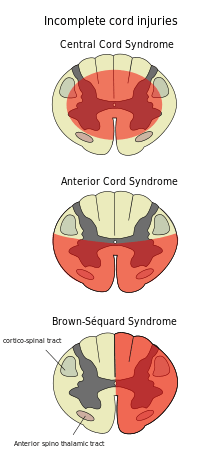

Central cord syndrome

Central cord syndrome, almost always resulting from damage to the cervical spinal cord, is characterized by weakness in the arms with relative sparing of the legs, and spared sensation in regions served by the sacral segments.[21] There is loss of sensation of pain, temperature, light touch, and pressure below the level of injury.[22] The spinal tracts that serve the arms are more affected due to their central location in the spinal cord, while the corticospinal fibers destined for the legs are spared due to their more external location.[22] The most common of the incomplete SCI syndromes, central cord syndrome usually results from neck hyperextension in older people with spinal stenosis. In younger people, it most commonly results from neck flexion.[23] The most common causes are falls and vehicle accidents; however other possible causes include spinal stenosis and impingement on the spinal cord by a tumor or vertebral disk.[24]

Anterior cord syndrome

Anterior cord syndrome, due to damage to the front portion of the spinal cord or reduction in the blood supply from the anterior spinal artery, can be caused by fractures or dislocations of vertebrae or herniated disks.[22] Below the level of injury, motor function, pain sensation, and temperature sensation are lost, while sense of touch and proprioception (sense of position in space) remain intact.[25][23] These differences are due to the relative locations of the spinal tracts responsible for each type of function.[22]

Brown-Séquard syndrome

Brown-Séquard syndrome occurs when the spinal cord is injured on one side much more than the other.[26] It is rare for the spinal cord to be truly hemisected (severed on one side), but partial lesions due to penetrating wounds (such as gunshot or knife wounds) or fractured vertebrae or tumors are common.[27] On the ipsilateral side of the injury (same side), the body loses motor function, proprioception, and senses of vibration and touch.[26] On the contralateral (opposite side) of the injury, there is a loss of pain and temperature sensations.[24][26]